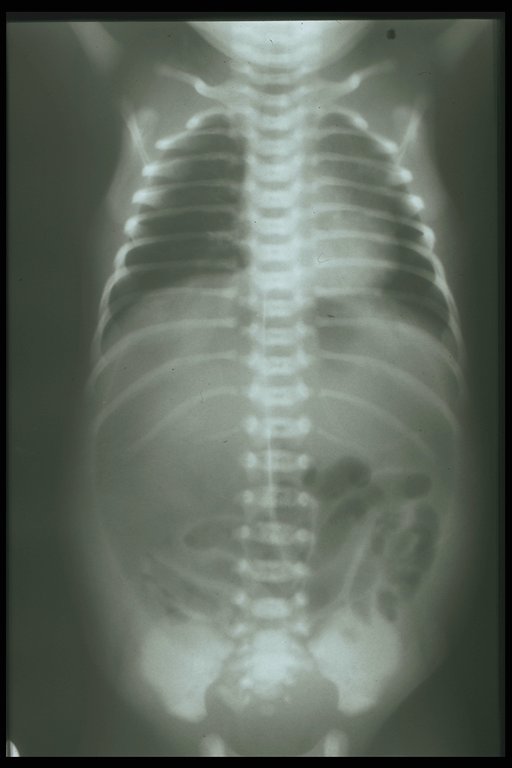

Large gas shadow at the central abdomen in the supine film and the well outlined falciform ligament (white line) indicates bowel perforation